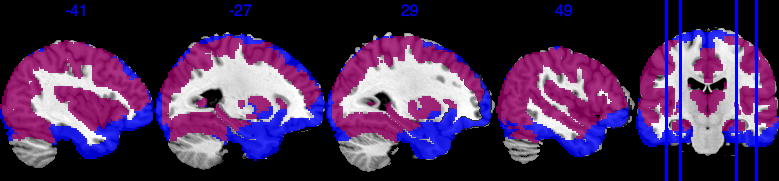

To define the analysis mask, we first define the inclusion rate at location to be , where is the set of all observed locations for individual . We define the group analysis mask as , i.e., the area where each voxel has at least 50% observed data. As shown in Figure 6, compared to where the inclusion rate is at least 50% (blue area), a vast area is missing from the group analysis mask (100% inclusion rate; purple area overlaying on top of the blue area), especially the bottom of the brain, including the orbitofrontal cortex and inferior temporal cortex, and notably the amygdala region important in this emotion task. In particular, the atlas we are using contains 110 brain regions, but the mask with 100% inclusion rate contains only 101 regions.